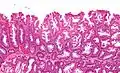

Histopathologie

La partie profonde des glandes est souvent élargie, a tendance à se diviser en deux ou trois branches et à s’horizontaliser, c'est-à-dire à se disposer parallèlement à la musculaire muqueuse et non pas perpendiculairement à elle, comme dans les polypes hyperplasiques conventionnels et les adénomes festonnés traditionnels.